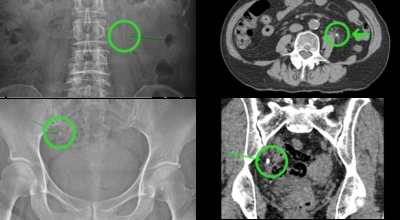

요로결석이란

수분 섭취 감소는 요로결석의 가장 중요한 발병 이유가 되는 것 이라고 합니다. 수분의 섭취가 떨어지면 요석결정이 소변에 머무르는 시간이 길어져 요석형성이 증가하게 되며 요로결석의 발생은 유전적인 소인이 있다는 것이 정설이나 후천적인 생활습관도 관련성을 보입니다.

남성이 여성에 대조해 2-3배 발생 위험성이 높고, 20~40대의 젊은 연령층에서 잘 발생하였지만였다고 하였으나 최근 고령층에서 발생이 증가하고 있으며 요로결석은 지리적으로 산이 많은 지역, 사막, 열대 지방에서 많이 발생하는데, 이는 음식, 온도, 습도 등이 복합적으로 작용하기 때문이라고 해요. 온도와 계절은 요로결석 발생에 중요한 요인으로 작용하지만, 여름에는 땀을 많이 흘리면서 소변이 농축되어 요로결석의 생성이 용이해진다고 해요.